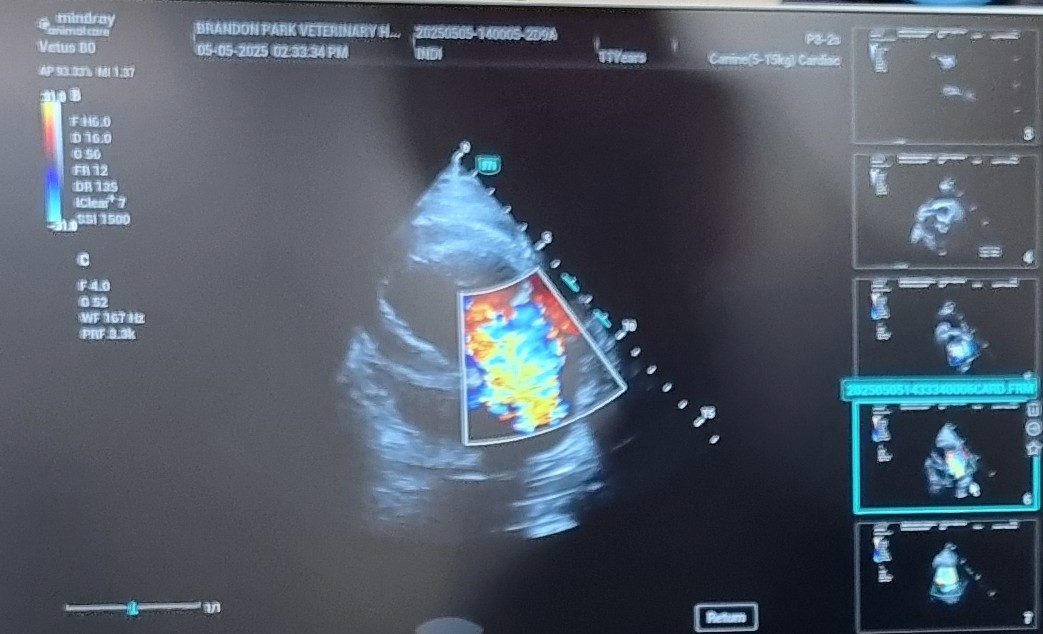

Heart Disease Evaluation

Our ultrasounds are essential in assessing heart conditions, providing critical information for treatment plans.

Heart Assessments

Heart function assessments that ensure optimal treatment plans for your pet